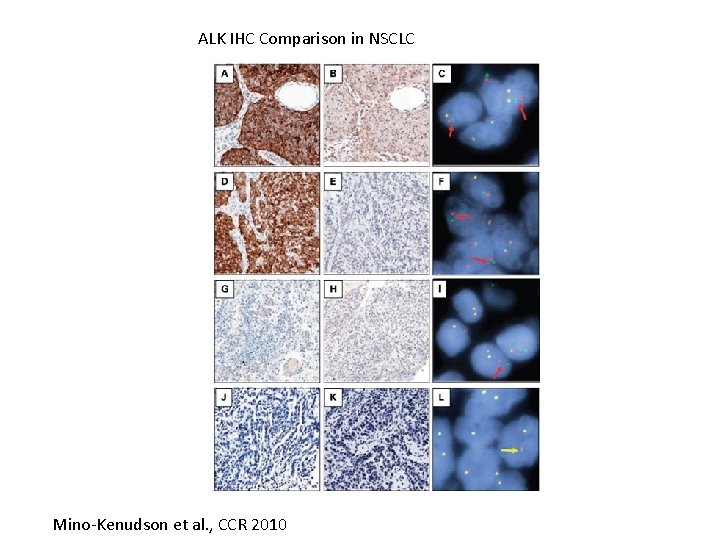

ALK IHC Comparison in NSCLC Mino-Kenudson et al. , CCR 2010